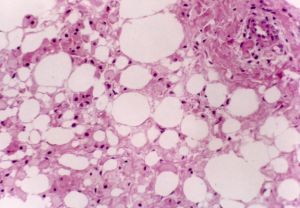

虎斑心是由於機體嚴重貧血等原因,心肌細胞發生脂肪變性,肌纖維彈性降低,心室擴展,肥大,呈局灶性或瀰漫性黃褐色,切面渾濁,結構不清。在左心室內膜下和乳頭肌周圍,在紅褐色(心肌纖維)的背景上出現灰黃色(心肌脂肪變性)條紋或斑塊,狀似虎斑,稱虎斑心。

虎斑心石蠟切片